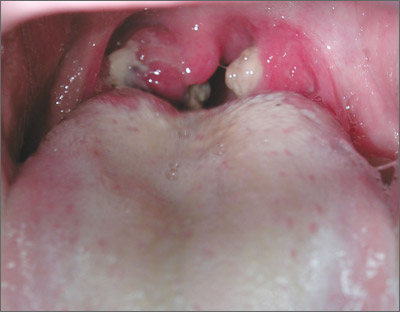

Throat and neck pain

The FP suspected that the patient had infectious mononucleosis caused by the Epstein-Barr virus. She performed an abdominal exam, but there was no evidence of hepatosplenomegaly. Other features of mononucleosis may include nausea, anorexia without vomiting, uvular edema, generalized symmetric lymphadenopathy, and lethargy.

The FP recommended supportive measures including ibuprofen and/or acetaminophen for pain and fever, plenty of fluids, and rest. The patient was sent to the lab for a Monospot test, and the result came back positive the following day. At that point, the FP also recommended avoidance of contact sports for the next few months because of the risk of splenic rupture associated with mononucleosis. At a follow-up appointment a week later, the patient was doing somewhat better but continued to have some fatigue, pharyngitis, and lymphadenopathy. Fortunately, this was the start of summer vacation for the student, so she was able to take time off to recuperate.